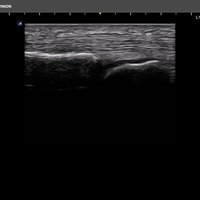

Für das X-CUBE i9 steht ein umfangreiches Schallkopfportfolio zur Verfügung. Somit kann das komplette internistische Spektrum inklusive der Kardiologie, aber auch Untersuchungen des Bewegungsapparates mit hochauflösenden Schallköpfen bis 25 MHz oder gynäkologische bzw. urologische Untersuchungen mit der Qualität eines Standsystems durchgeführt werden.

Linear-Sonden

• SL3-19H (3-19 MHz) für Ultraschalluntersuchungen in Bereichen MSK, Vaskulär, Weichteile, Pädiatrie, EM

• L3-8H (3-8 MHz) für Ultraschalluntersuchungen in Bereichen Brust, EM, MSK, Vaskulär, Weichteile

• L10-25H (10-25 MHz) für Ultraschalluntersuchungen in Bereichen MSK, Vaskulär, Weichteile, EM